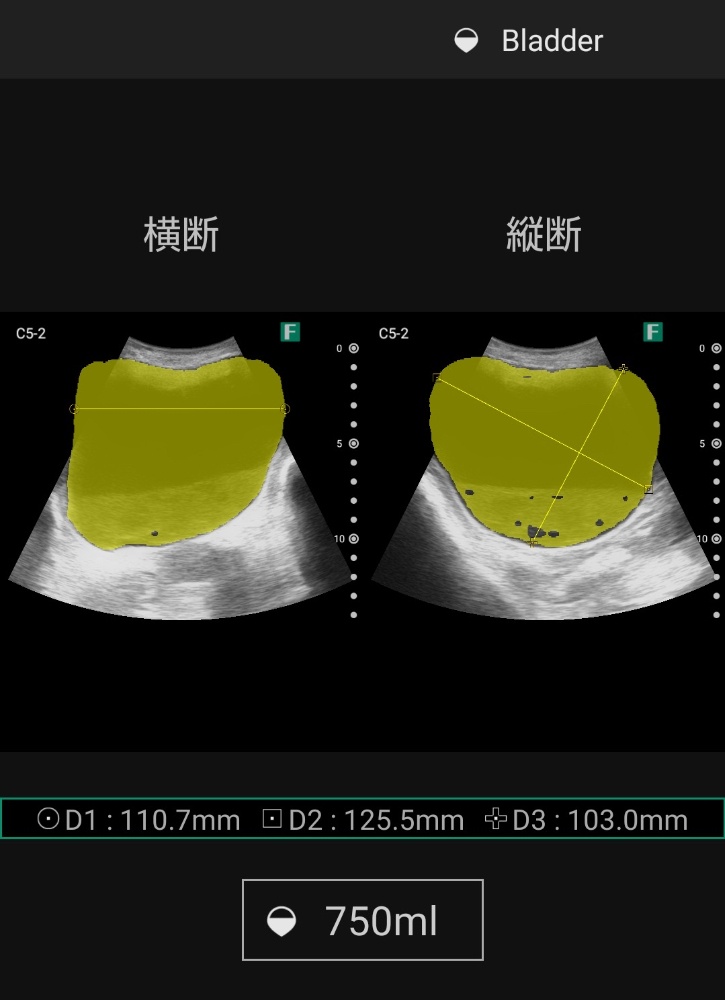

エコーを活用した看護を実践しています

↓画像をタップすると拡大します🔍